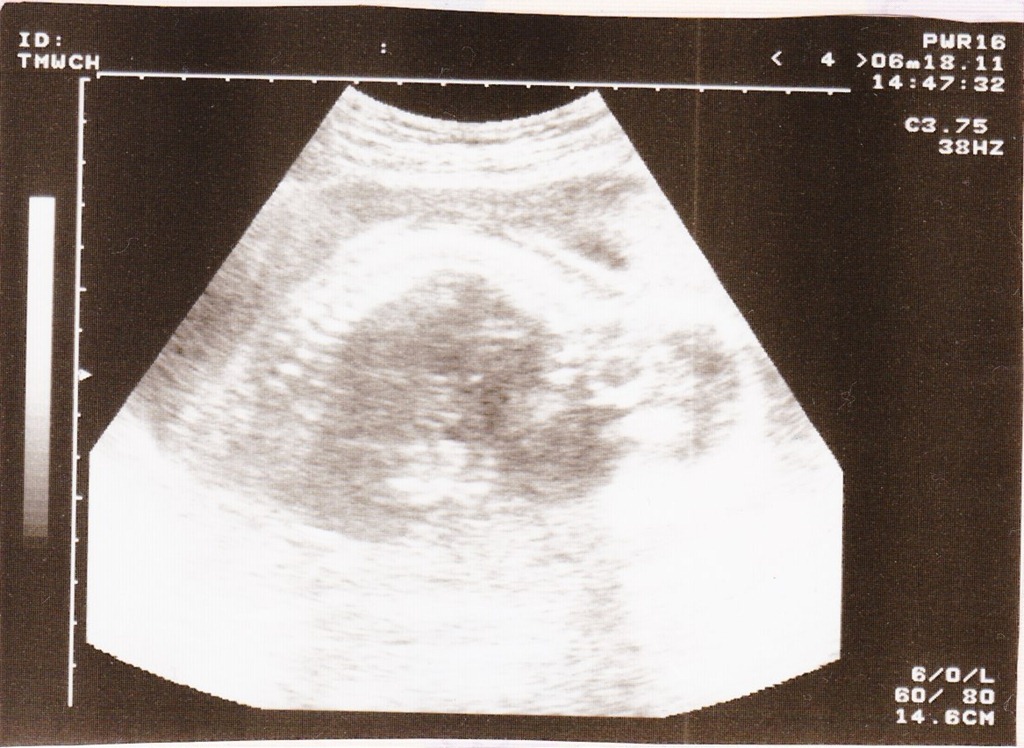

100/6/18:這時候的我已經22周了,隨著我長大,超音波漸漸沒辦法拍到我的全身,這次的照片拍的是我的大頭及脊椎骨彎曲的樣子,今天測出心跳每分鐘160次,頭圍正常,都很OK~相較於平常等待給林陳立醫生伯伯產檢的兩小時,這次只花了30分鐘就完成,非常的有效率。

![]()